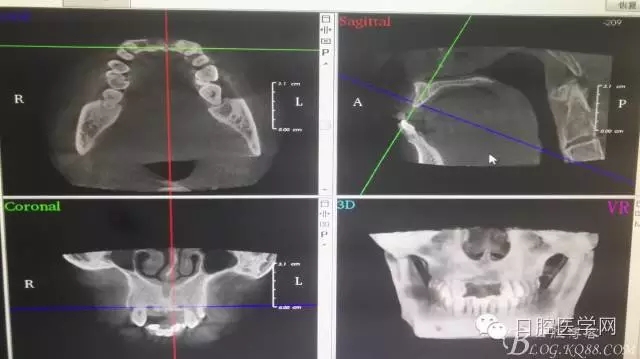

一例上前牙缺失后GBR骨再生技術(shù)

為他院轉(zhuǎn)診患者。男,無(wú)吸煙史,前牙因齲壞治療后,外力折斷導(dǎo)致拔除?,F(xiàn)拔除該牙后兩個(gè)多月。 左上區(qū)域骨寬度不足,計(jì)劃植入種植體同期GBR。

左上區(qū)域骨寬度不足,計(jì)劃植入種植體同期GBR。